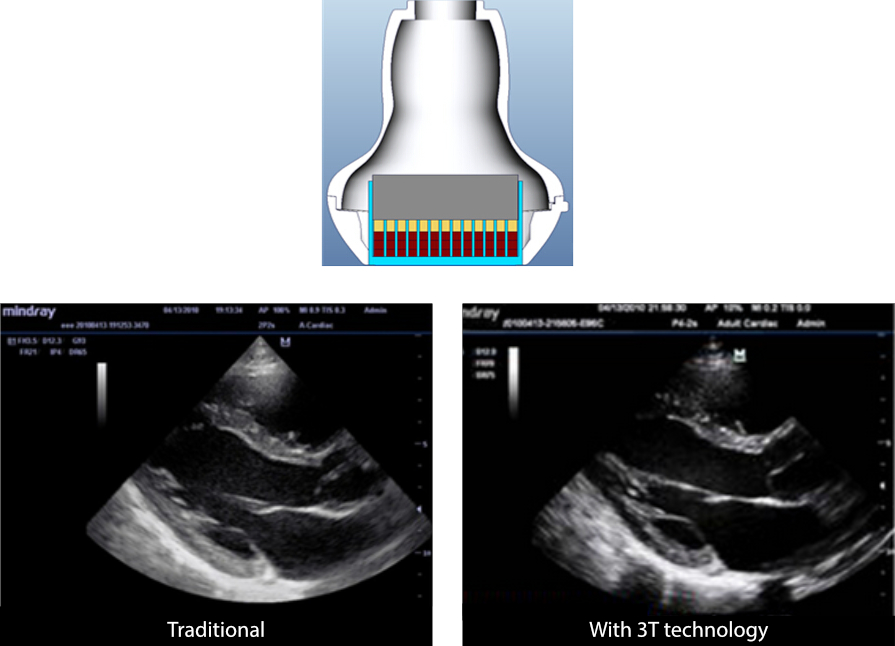

3T Transducer Technology?

Tecnología patentada de transducción de Mindray para aumentar el ancho de banda de la imagen, así como la eficiencia de transmisión.

¬Ј?Dise?o de triple capa coincidente para una mayor sensibilidad, ancho de banda m√°s amplio y S/R mejorado

¬Ј?Dise?o de corte total para reducir el ruido diaf√≥nico y mejorar la directividad y la resoluci√≥n lateral

¬Ј?Dise?o con regulaci√≥n t√©rmica para una mejor transmisi√≥n ac√Їstica